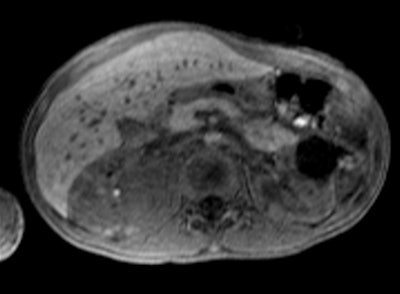

StarVIBE is a new pulse sequence that enables free-breathing, contrast-enhanced liver imaging for patients who are unable to easily manage breath-holding, such as those who are old, very ill, or young. Meanwhile, TWIST-VIBE is intended for more accurate contrast imaging in dynamic liver MRI scans for all patients and lesions, allowing faster liver imaging with full 4D coverage.

With Siemens' StarVIBE technology, no breath-hold is needed. The images above and below show the increase in image quality with StarVIBE. Images courtesy of Siemens.